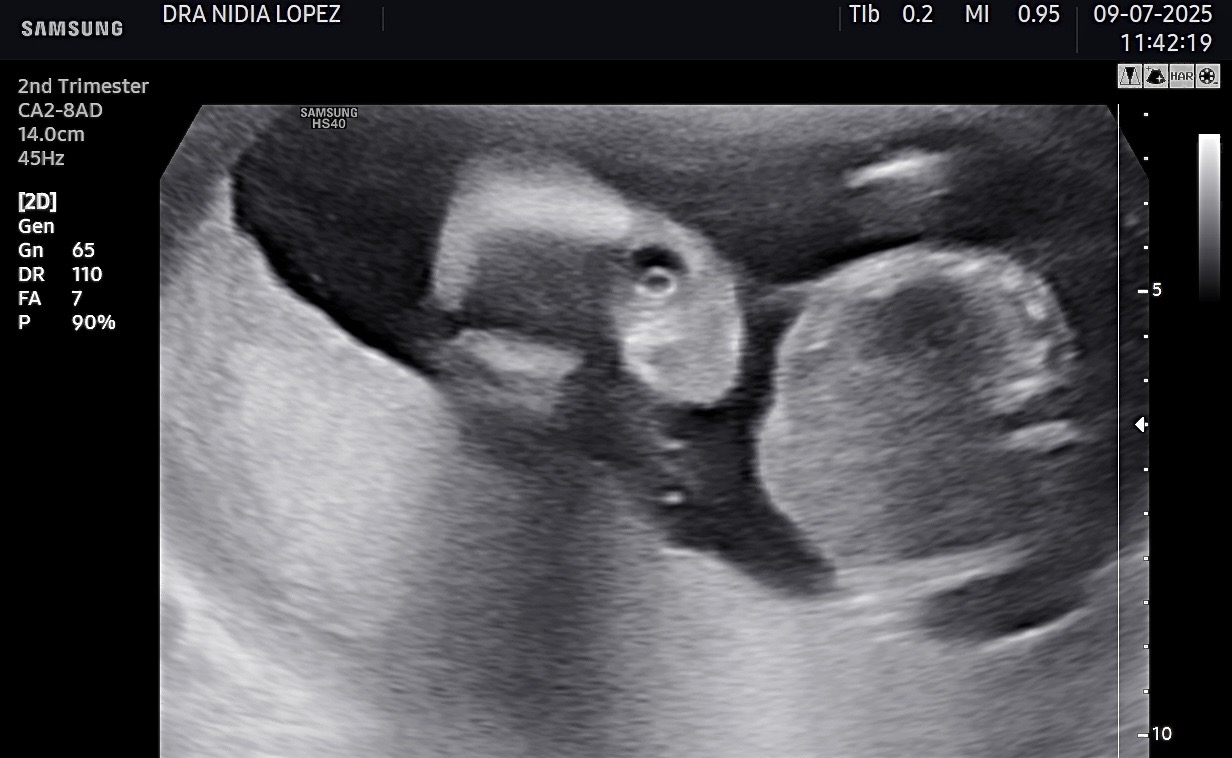

I lived in US all my life, after 30yrs I was sent to a country I knew nothing of where medical insurance is not provided which puts many of us at risk. I’m currently pregnant, which those who know me know I was NEVER able to another kid, 23yrs later I have a new baby, she’s a TRUE BLESSING and definitely a MIRACLE yet the pregnancy has had a lot of negative loopholes as I am extremely high risk. Im grateful we’ve gotten this far yet the father of the baby doesn’t seem to care much about the financial burden . He became very abusive to the point were the week after our first ultrasound he physically hurt me in a brutal way. I had to let go if I wanted my baby girl to survive. It breaks my sole as it has many single mothers to know we have to do this alone. If all goes well with my pregnancy my girl will be born next month yet I don’t have the funds to birth her in a hospital were they treat extreme high risk pregnancies. I want my baby. I never been the type to ask for help, yet here I am, I need help. Anything will be appreciated with all the strength left in me.